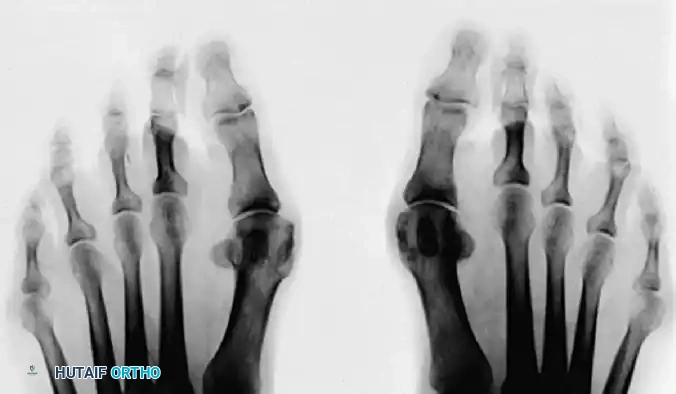

The Axial Sesamoid View

The axial sesamoid view should always be obtained if a sesamoid pathological condition is suspected. It provides a tangential look at the articular surface, the crista, and the joint space.

FIGURE 81-102 A: Hallux valgus deformity on AP radiograph.

FIGURE 81-102 B: On the axial sesamoid view, degenerative changes are present with subluxation of the sesamoids laterally.